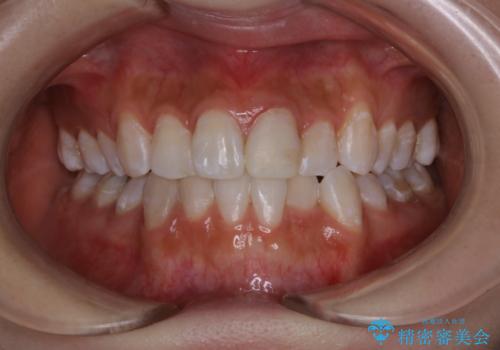

インビザライン矯正治療のスキャニング前のPMTC

担当医 歯科衛生士

銀歯をセラミックに変える前にPMTCで現状の汚れをきれいに除去

invisalignでの矯正治療が終了した方のPMTC

日々の磨き残しをPMTCできれいに

歯科医院で初めてのクリーニング PMTC30分コース